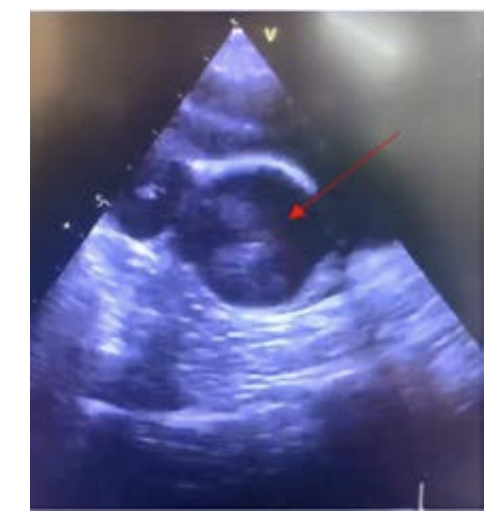

The patient returned to the clinic 48 hours after the first attendance and presented persistent cough, lack of appetite, and subfebrile temperature (37.5° C). Physical examination was unremarkable. A chest CT, without contrast, conveyed bilateral ground glass pulmonary opacities, more evident in the peripheral pulmonary segments, with less than 50% involvement (Figure 1). The diagnosis of COVID-19 was confirmed by RT-PCR. The patient was hospitalized and intravenous antibiotic therapy with Ceftriaxone (1g IV) and Azithromycin (500mg PO) was performed. In the midst of the hospitalization, the patient developed persistent fever, worsening of the breathing pattern (Sat O2 90% and respiratory rate 30 breaths per minute), and had axillary temperature of 37.9°C, a heart rate of 90 bpm, which led to a nasal catheter at 4L/min. Through a physical pulmonary examination, it was possible to assess that she had muffled breath sounds at the bases, with crackling rales. Blood tests showed elevated inflammatory markers (Table 1).

The clinical state worsened (Sa O2 90% - 88%, RR 28 breaths per minute), and the new CT (Figure 2) pointed to bilateral laminar pleural effusion and to marked increase in diffuse and symmetrical ground-glass pulmonary opacities. The extent of pulmonary involvement was estimated to be greater than 75%. Therefore, she was transferred to the ICU due to the worsening of the respiratory condition and received supplementary oxygen, through a high-flow mask (10L/min, Sa O2 89% and RR 44 breaths per minute).